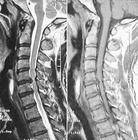

就诊科室:中医科 中医综合易感人群:无特殊人群需做检查:脊柱MRI检查 脊柱触诊 脊柱活动度 脊柱压痛与叩击痛 神经系统检查 脊柱椎体平扫常用药物:颈痛片 颈复康颗粒 颈舒颗粒 根痛平颗粒 藤黄健骨片 氨糖美辛肠溶片 腰息痛胶囊 藤黄健骨丸 灵仙跌打片 根痛平片 吲哚美辛巴布膏 骨刺平片 骨刺消痛胶囊 沉香十七味丸 牛痘疫苗致炎兔皮提取物注射液 骨刺宁胶囊 颈通颗粒 颈痛灵药酒 根痛平胶囊 抗骨增生片 盐酸乙哌立松片 伸筋丹胶囊 通迪胶囊 复方七叶皂苷钠凝胶 注射用复方骨肽典型症状:耳鸣 乏力 肌肉萎缩 腱反射消失 颈部疼痛 颈肩痛 手麻 头痛 眩晕传染方式:无传染性治疗方式:无传染性相关疾病:颈椎病 植物神经功能紊乱 痹证 筋痹 顽痹